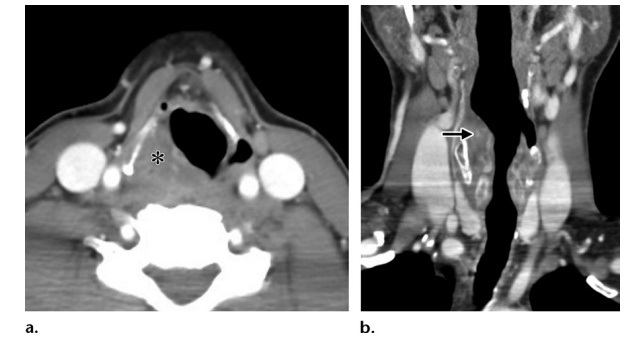

Рис 1. Надгортанная гематома у мужчины 25 лет с болью в шее после колющей травмы ручкой. Не было ни разрыва кожи, ни раневого канала инородного тела при осмотре, чтобы предположить проникающую травму. (а) На КТ в аксиальной плоскости видна правосторонняя надгортанная гематома со сглаживанием грушевидной пазухи (*). (b) На КТ в корональной плоскости видны деформация и сужение дыхательных путей из-за надгортанной гематомы (стрелка).